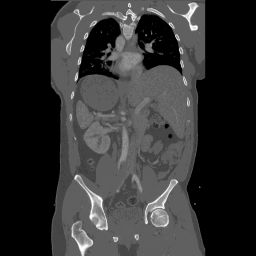

ScribblePrompt The main goal of the tool is to simplify the segmentation process of medical images, which is crucial in applications such as tumor detection and organ contouring. Instead of relying on a large amount of manually annotated data, the tool allows users to guide the model to optimize the segmentation results with a small amount of input (such as simple scribbles or points). This approach reduces the time and effort of medical experts in image annotation while ensuring the accuracy of segmentation.

Effect examples

![]() | ![]() | ![]() |